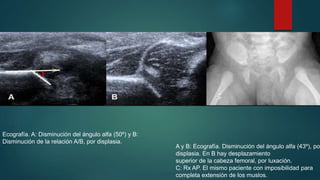

Ecografía. A: Disminución del ángulo alfa (50º) y B:

Disminución de la relación A/B, por displasia.

A y B: Ecografía. Disminución del ángulo alfa (43º), por

displasia. En B hay desplazamiento

superior de la cabeza femoral, por luxación.

C: Rx AP. El mismo paciente con imposibilidad para

completa extensión de los muslos.